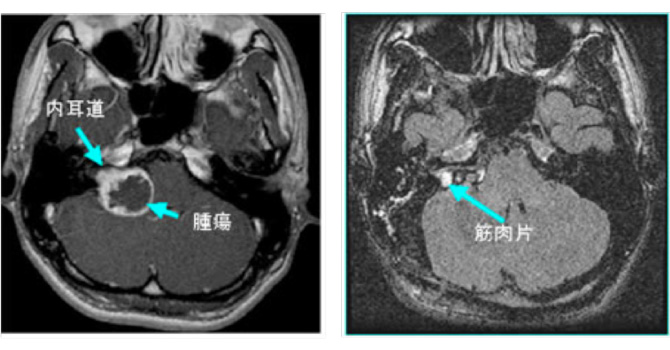

図1:20代男性 聴神経腫瘍

(左図)術前MRI:術前聴力は10dB

(右図)術後MRI:内耳道に筋肉片がおかれている術後聴力は温存16dB 顔面麻痺はなし